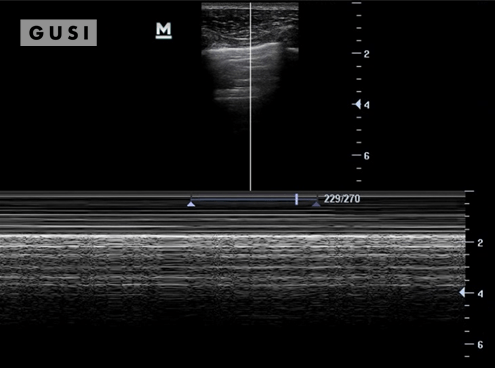

|

|

During the 2017 World Taekwondo Championships in Muju, Korea, a 30-year-old female athlete from Hong Kong was kicked in her left eye by an opponent. She reported fluctuating vision accompanied by pain during eye movement. A POCUS examination of the affected eye indicated a vitreous hemorrhage, with no evidence of lens subluxation or globe rupture.

On the ultrasound, as the athlete moved her eyes laterally, the hemorrhage (denoted by a white arrow) exhibited a swirling pattern within the globe, consistent with her eye movement. The athlete was promptly referred to a specialized medical center for an ophthalmology consultation, where the diagnosis of vitreous hemorrhage was confirmed. The patient was subsequently discharged from the Emergency Department with specific precautionary measures.